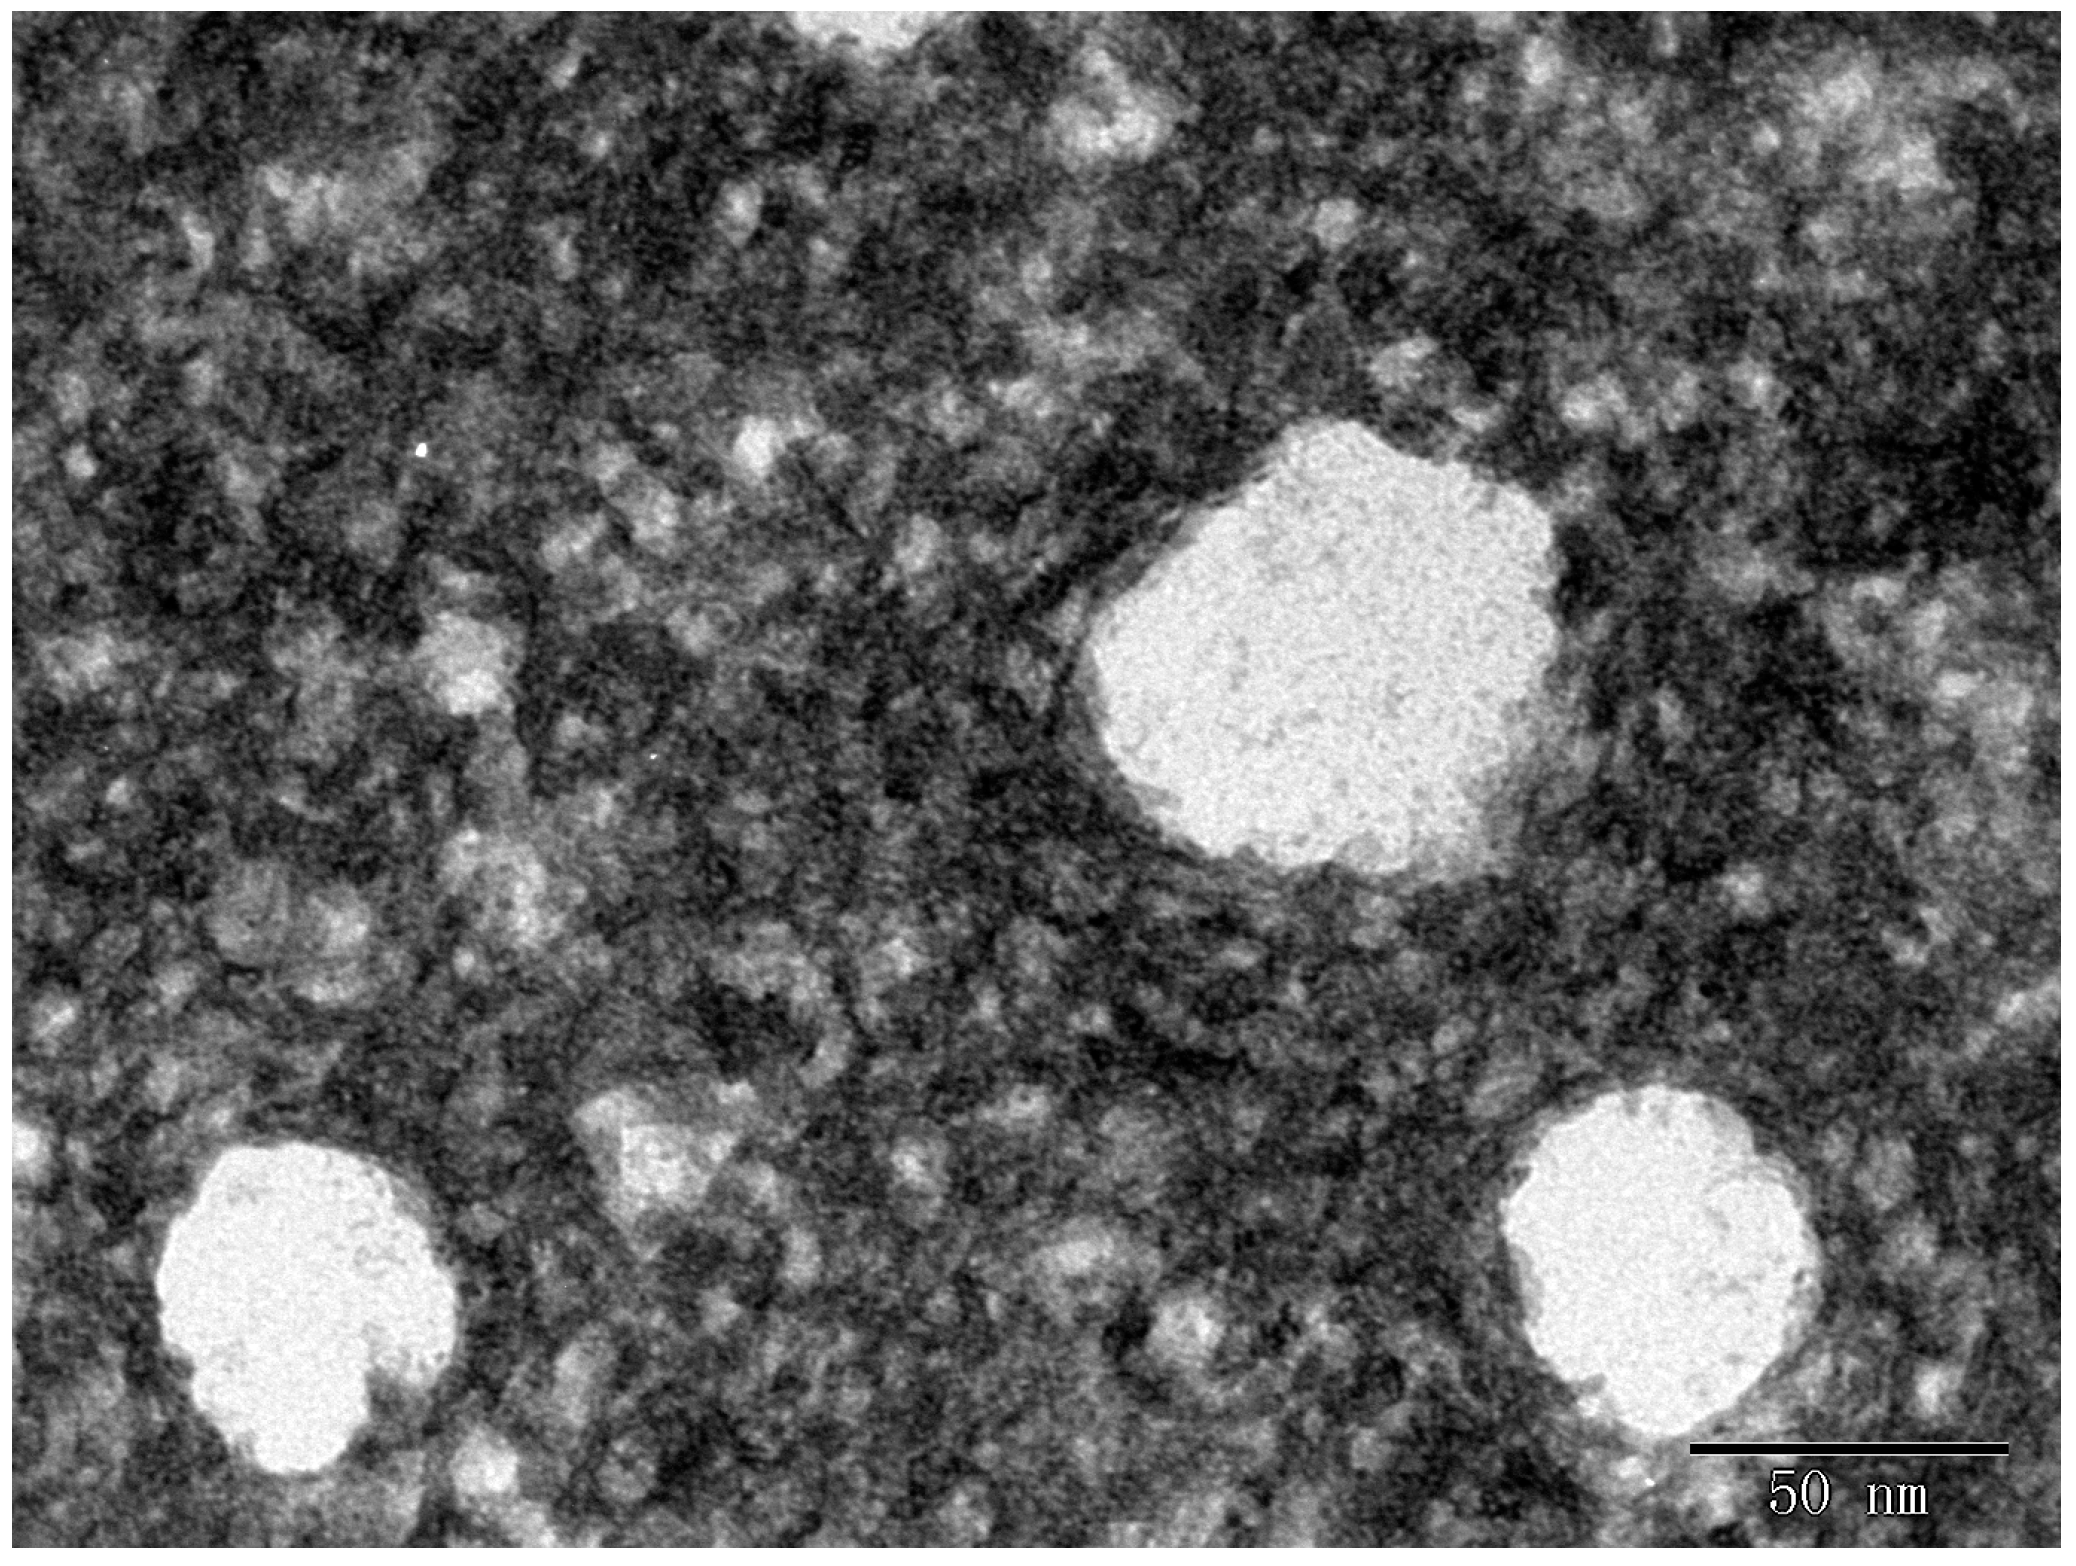

3.8. Morphology

2.3. Characteristics of RSV Emulsion